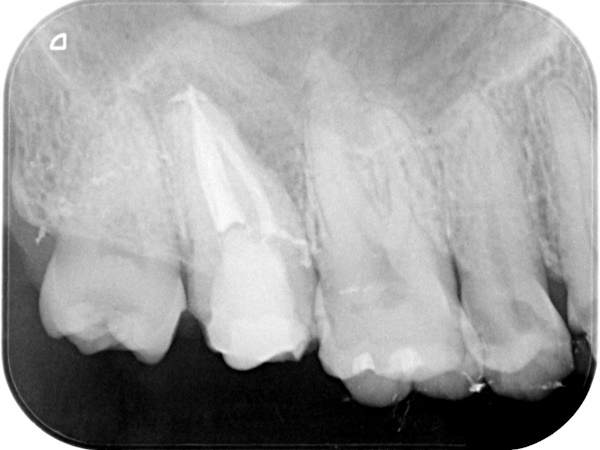

【 上の歯の精密根管治療 】

術前から術後までの治療の流れ

根管治療終了時

根管治療終了後3か月経過